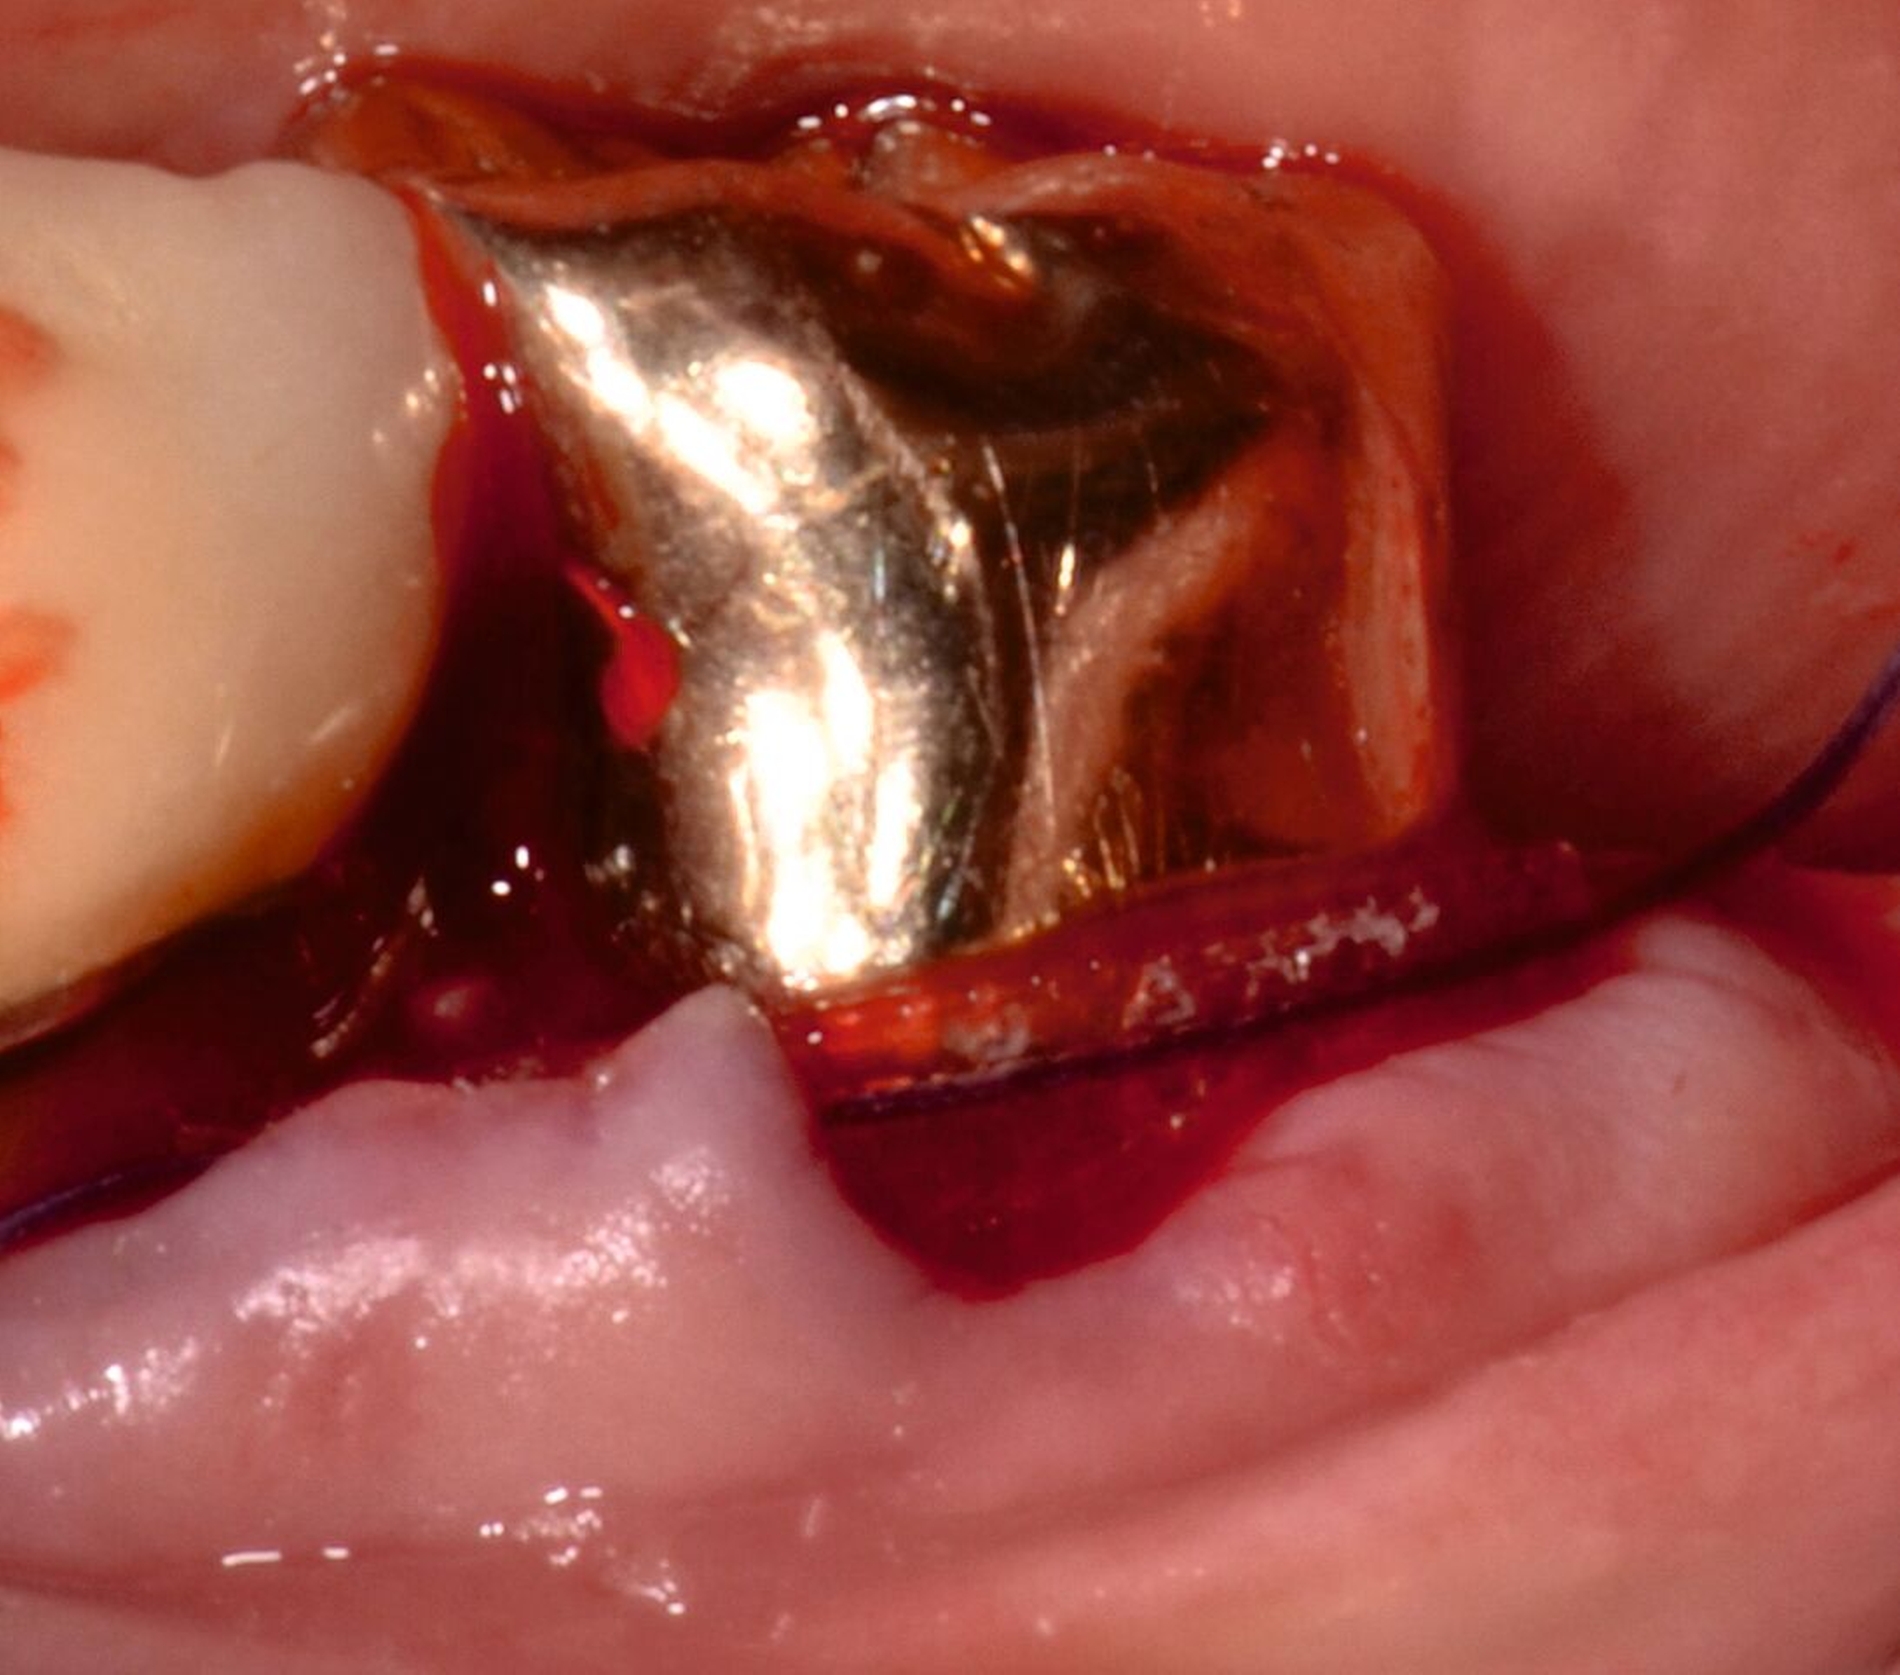

3. Regenerative Parodontalchirurgie

Ziel ist es, einen ausreichenden Zugang zum Defekt für eine sorgfältige Instrumentierung und die Applikation des Biomaterials zu erhalten. Bei isolierten Defekten können vertikale Entlastungsinzisionen verwendet werden. Alternativ kann der Lappen nach lateral zu den benachbarten Zähnen erweitert werden. Keratinisiertes Gewebe sollte durch intrasulkuläre Inzision und die Anhebung eines Mukoperiostlappens erhalten werden. Das Granulationsgewebe wird entfernt und die freiliegenden Wurzeloberflächen werden sorgfältig mit Handinstrumenten, oszillierenden Scalern (optional mit fein diamantierten Spitzen) oder rotierenden Instrumenten gereinigt. Wurzelanomalien wie Schmelzvorsprünge/-perlen sollten entfernt werden. Wenn EMD Teil der Regenerationsstrategie ist, wird es in der Regel nach einer zweiminütigen Wurzelkonditionierung mit Ethylendiamintetraacetat (EDTA) und Spülung mit steriler Kochsalzlösung angewendet. Anschließend kann ein Knochentransplantat/-ersatzmaterial verwendet werden, um den Furkationsdefekt aufzufüllen.

Alternativ kann eine GTR-Barrieremembran mit oder ohne zusätzlichen Defektfüller appliziert werden. Die Barrieremembran wird mit einer resorbierbaren Umschlingungsnaht befestigt, um den Furkationseingang abzudecken und die Wund- und Koagulumstabilisierung zu fördern. Um eine vollständige Abdeckung der Barriere zu ermöglichen, kann das Periost durchtrennt werden, um den Lappen leicht koronal zu verschieben. Der Lappen wird mit einer Umschlingungsnaht und Einzelknopfnähten über den vertikalen Entlastungsinzisionen oder mit interdentalen Nähten im Fall eines lateral extendierten Lappens in einer koronalen Position gesichert. Der Patient wird angewiesen, für einen Zeitraum von bis zu vier Wochen auf die mechanische Plaqueentfernung im Operationsgebiet zu verzichten. Während dieser Zeit werden Chlorhexidin-Spülungen oder -Gel verwendet. Der Patient kehrt zur Kontrolle der Wundheilung nach ein und zwei Wochen zurück, wenn die Nähte entfernt werden. Die Interdentalhygiene und die mechanische Plaqueentfernung werden nach vier Wochen wieder aufgenommen. Zudem wird ein individuelles Recallprogramm zur unterstützenden Parodontitistherapie (UPT) festgelegt.